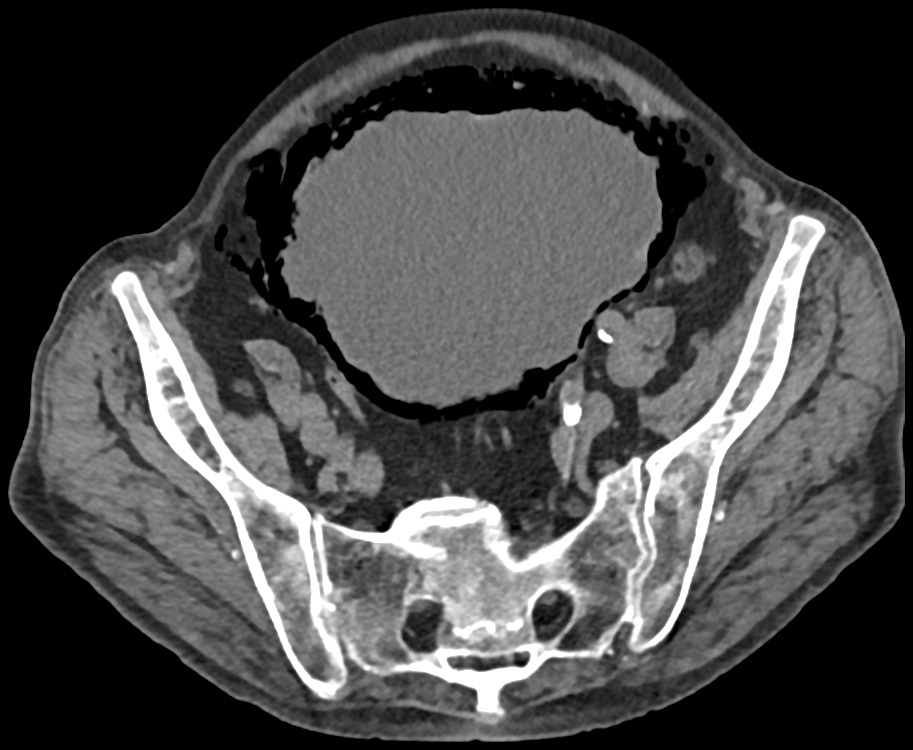

- Röntgenfoto's: Omdat ze verkalkt zijn, zijn flebolieten goed zichtbaar op röntgenfoto's.

- CT-scans: Ook op CT-scans zijn ze duidelijk te zien.